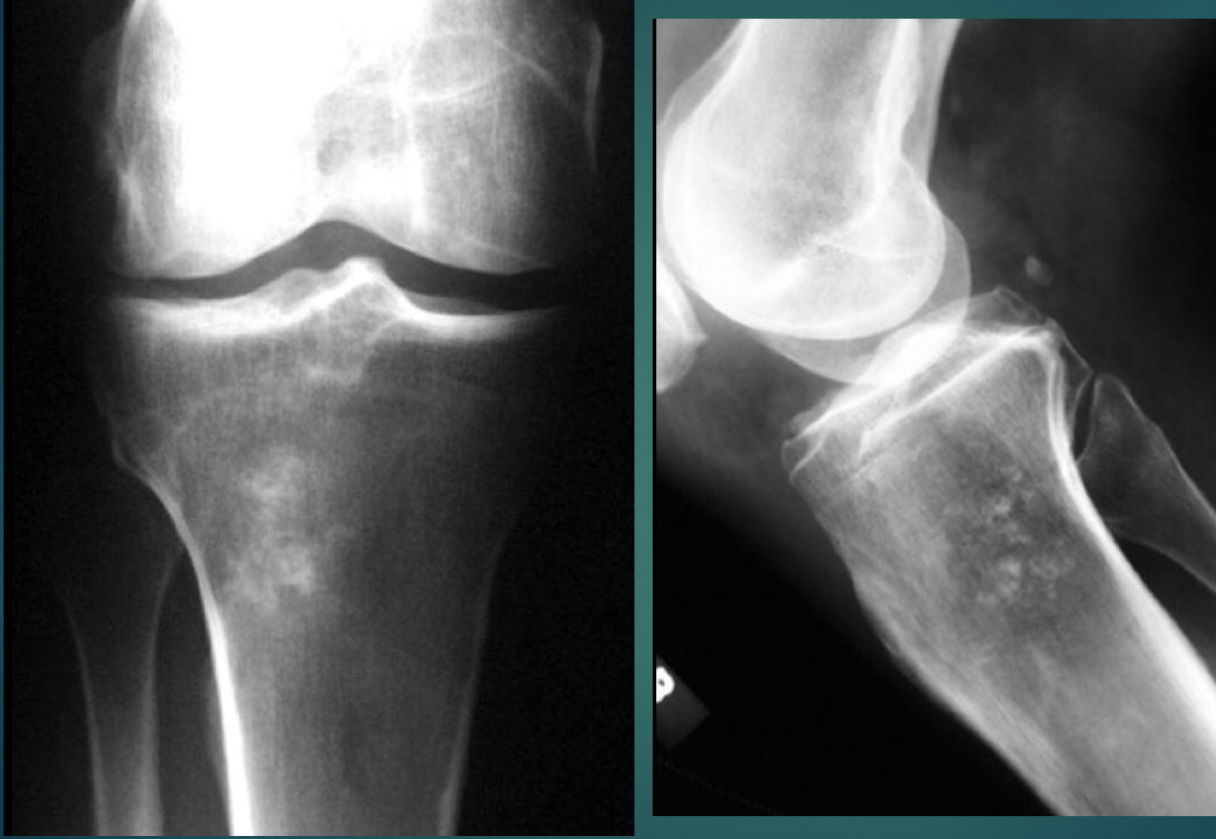

28 YO M. No history provided.

• Lytic, soap bubbly

• Closed growth plates

• Location at the knee

Think: Giant Cell Tumor

16 Y O M. No history provided.

• osteolytic lesion

• Open growth plates

Think: Chondroblastoma (opposite of GCT. Chondroblastoma will cross open growth plates.)